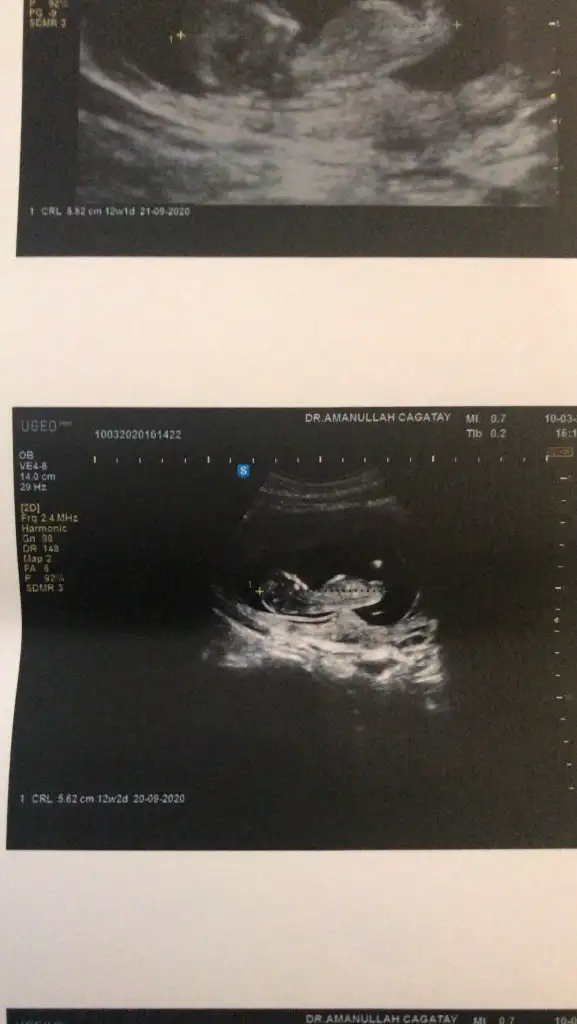

Kız sanki emin olamadım başka usgde paylaşınKızlar tahminde bulunabilirmisiniz ikiz bebekler 12 hafta 1 gunlikler

rBu kadar usg görüntüleri var malesef

9+3 haftada nub tahmini olmuyor nub için 11 yada 12 yada 13 haftaları paylaşınelimdeki tüm usg görüntüleri bunlaryeterli olur mu ki tahmin için